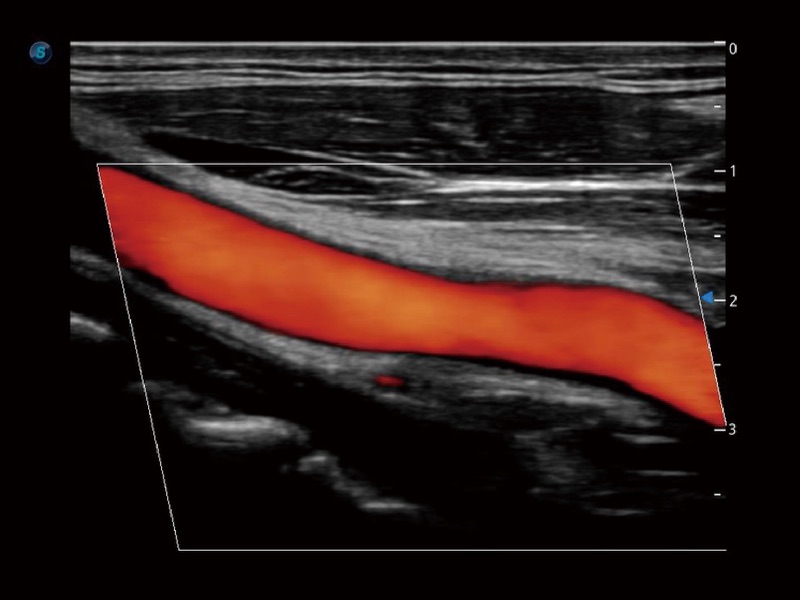

• 血管内中膜自动测量 Auto IMT

血管内中膜的厚度值是预测心血管疾病风险的重要指标,Auto IMT可以实现血管近场和远场内中膜厚度的自动测量,为临床提供快捷有效的诊断工具。